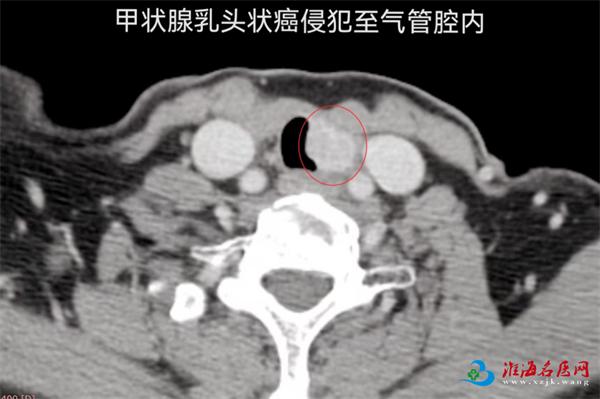

2019年,张女士因甲状腺乳头状癌接受了甲状腺全切术及碘-131治疗。2022年,因颈部淋巴结转移再次手术,术后长期口服靶向药物控制病情。2025年10月,她开始出现咯血症状,检查发现肿瘤在左侧气管旁复发,并已侵犯气管壁,这正是导致她咯血的原因。由于患者高龄、既往多次手术及放疗导致颈部解剖结构复杂、粘连严重,手术重建气道的风险极高,治疗一度陷入困境。